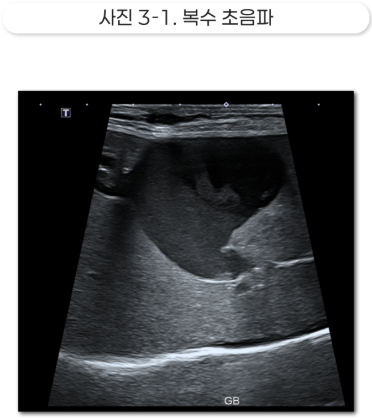

Etc: 담낭 내 슬러지 다수, 양측성 부신 비대